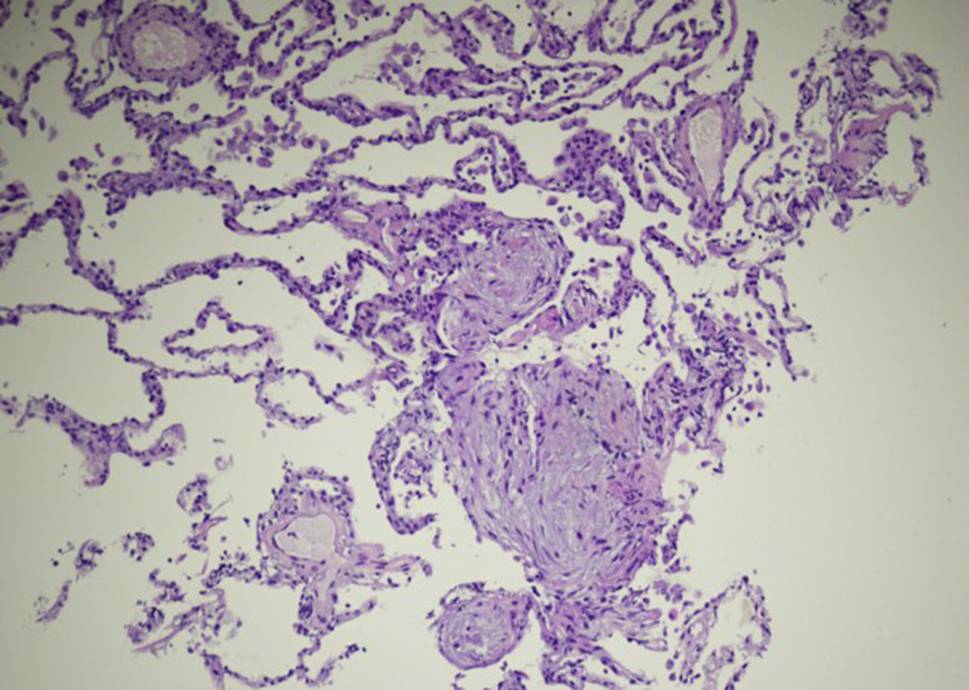

Fig. 1

Posterior-anterior Chest X‑ray from 22 April and 4 May showing substantial spontaneous improvement of the interstitial opacities and reticular densities

At the follow-up visit on 4 May originally intended to discuss potential treatment options following histological verification of organizing pneumonia, the patient reported substantial spontaneous improvements in well-being and dyspnea, prompting repeated functional assessments. Compared to previous testing lung volumes were normalized (TLC 98%) and gas exchange improved (DLCO 70%, paO2 81 mm Hg, paCO2 29 mm Hg, AaDO2 33 mm Hg). Chest X‑ray findings were also substantially improved (Fig. 1). Given the patients current clinical and functional status consensual agreement was made not to treat with systemic corticosteroids. Follow-up by chest X‑ray and pulmonary function tests were scheduled. The final diagnosis was organizing pneumonia following Covid19.